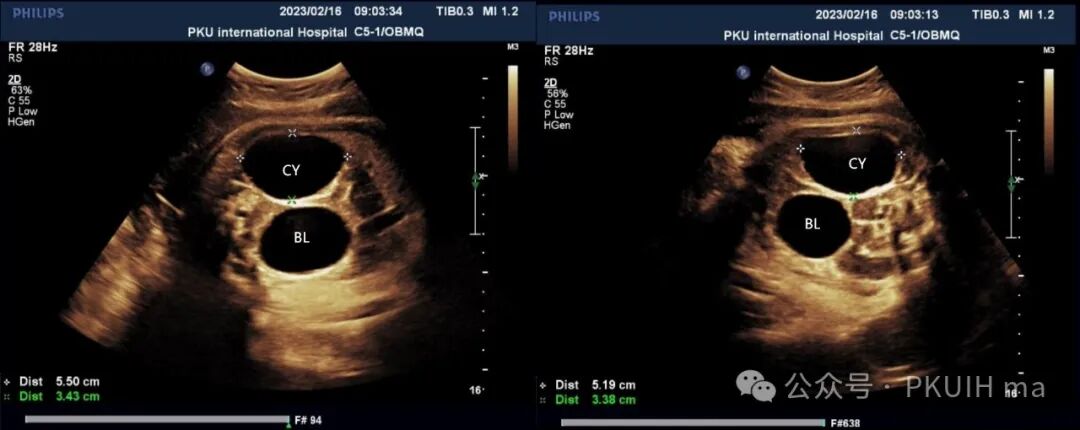

在随后的随访观察中(如下图)发现囊肿大小和内部回声有变化。最终考虑是卵巢出血性囊肿(卵巢扭转待除外)